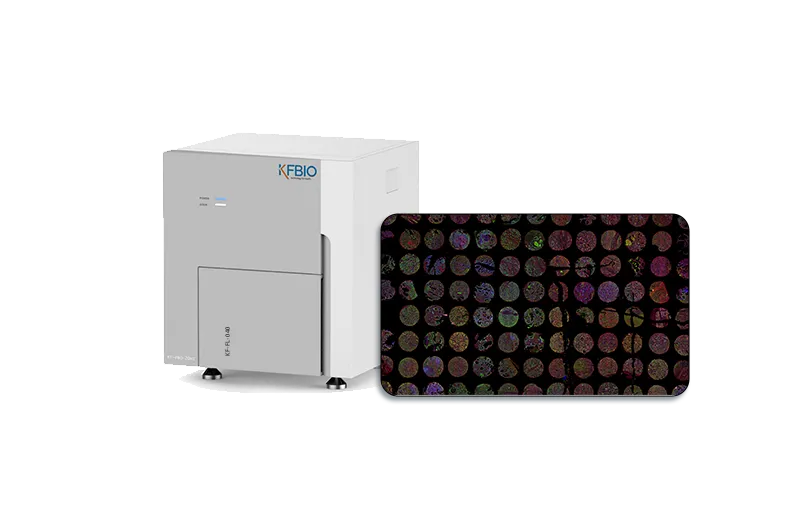

KF-FL-005

Digital Pathology 5

Slides Scanner fluorescence

Fast, High-precision,Stable, Clear

Scientific research, clinic,

tumor micro environment